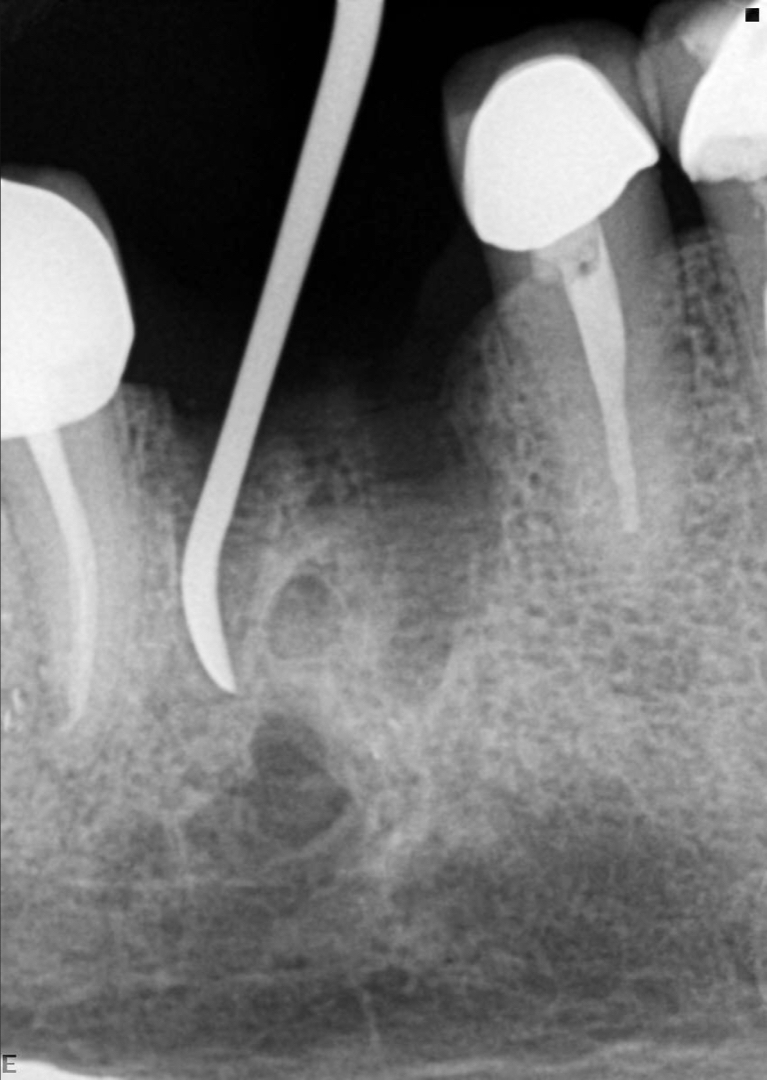

In this first case, the patient, who lived abroad and was unable to travel at the time, had swelling of her right mandible (Fig. 6), had had breast cancer and had been under bisphosphonate treatment for 18 months. She sent a panoramic radiograph (Fig. 7), and this showed a minor apical infection of the mandibular right first molar, which had undergone endodontic treatment. A CBCT scan was then taken, and from examining her scan, we could clearly see an area of bone densification (Fig. 8). This should be a red flag because this indicates the start of bone necrosis.

7: Panoramic radiograph showing a minor apical infection of the mandibular right first molar and endodontic treatment.